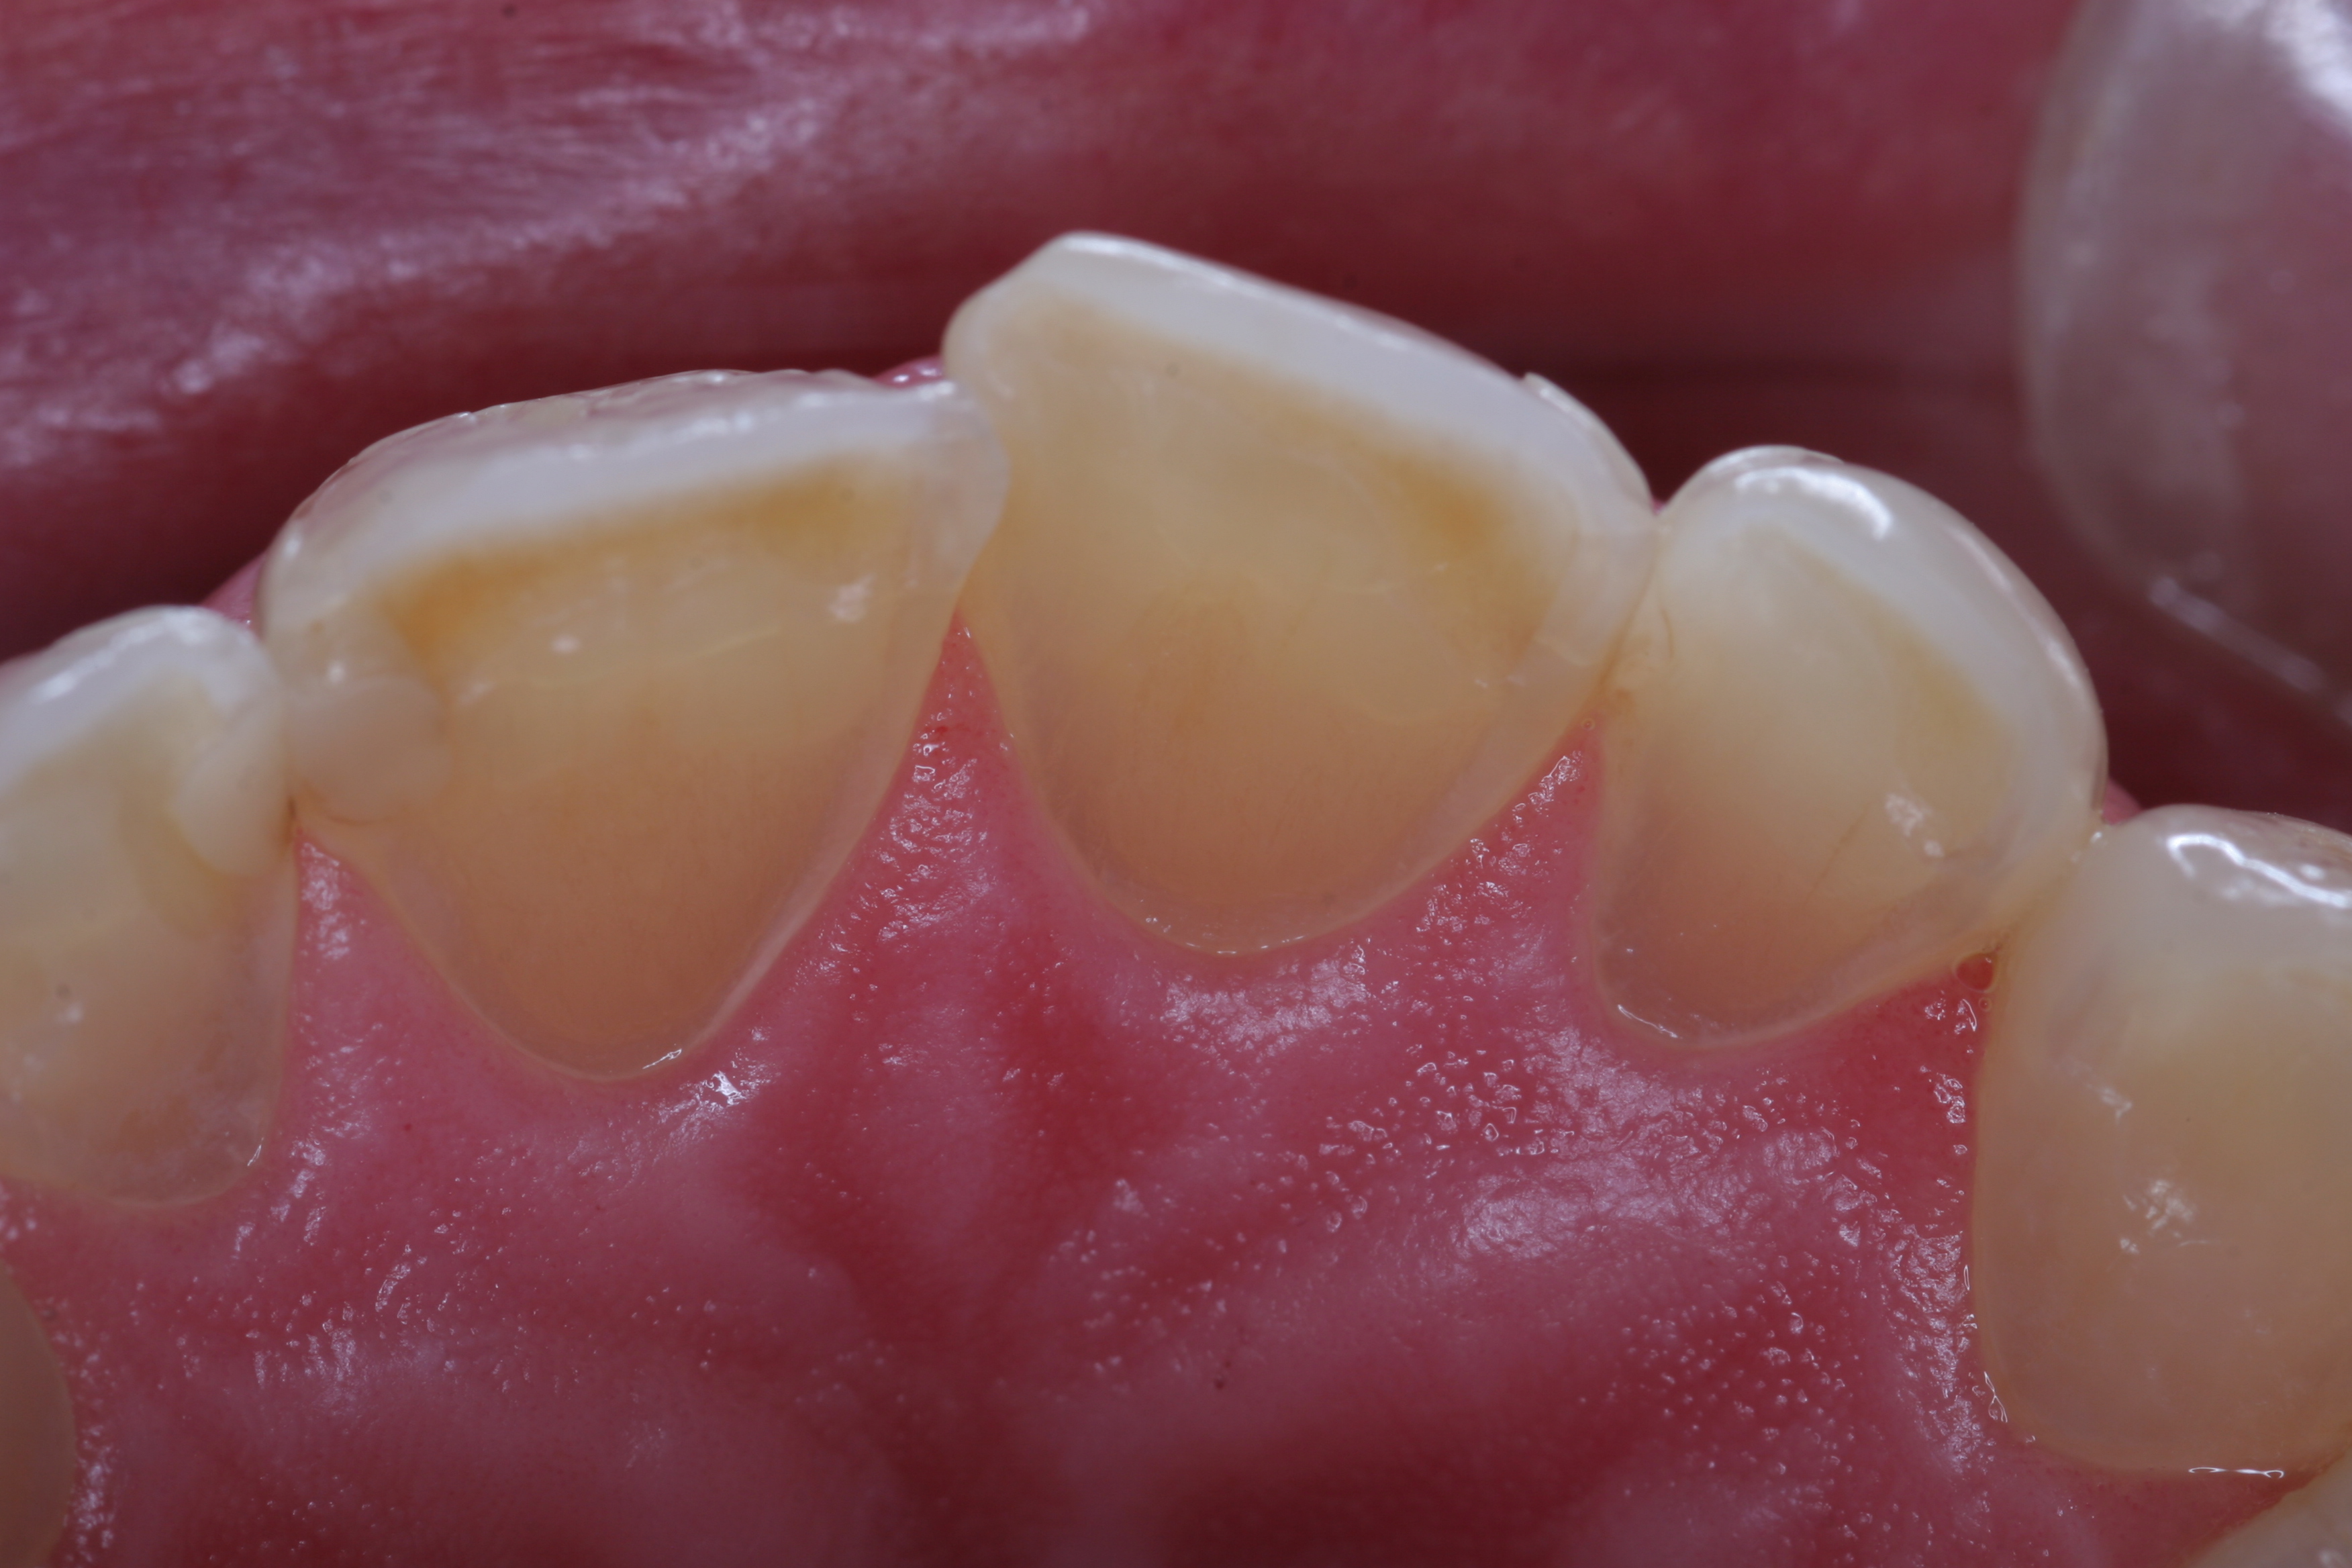

(6.) A common form of gastric erosion results from regurgitation, and presents with prominent involvement of the maxillary anterior lingual surfaces.

Figure 6